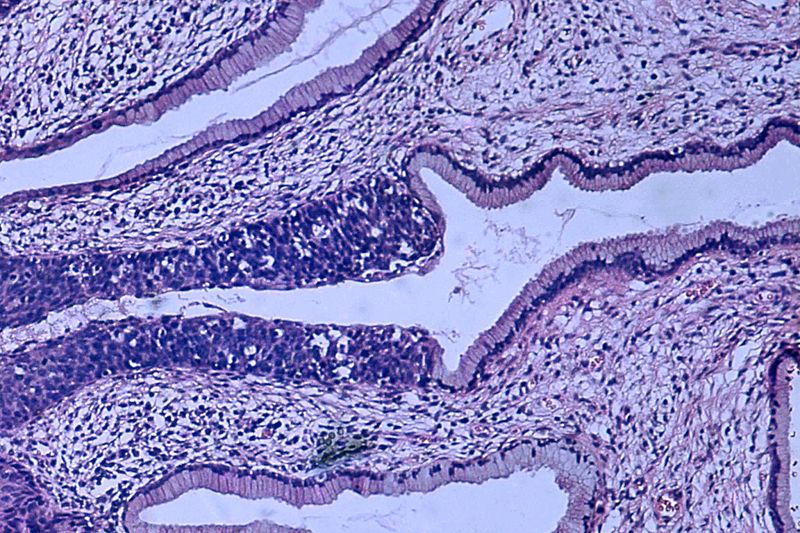

>>>Biopsja

Biopsja jest badaniem medycznym powszechnie wykonywanym przez chirurga, radiologa interwencyjnego lub kardiologa interwencyjnego. Proces ten polega na pobraniu próbki komórek lub tkanek do badania w celu określenia obecności lub zakresu choroby. Tkanka jest następnie utrwalana, odwadniana, osadzana, sekcjonowana, barwiona zanim zostanie ogólnie zbadana pod mikroskopem przez patologa; może być również analizowana chemicznie. Biopsje są najczęściej wykonywane w celu uzyskania wglądu w ewentualne stany nowotworowe lub zapalne. >>>

Patologia

Patologia to dziedzina medycyny, która zajmuje się badaniem chorób oraz ich wpływem na organizm. Koncentruje się na analizie zmian morfologicznych i funkcjonalnych, które zachodzą w tkankach i narządach w wyniku procesów chorobowych. Patolodzy wykonują biopsje, sekcje zwłok oraz analizy histopatologiczne, aby zrozumieć mechanizmy chorób, ich przyczyny oraz skutki. Dzięki tym badaniom możliwe jest postawienie dokładnych diagnoz, co wpływa na dalsze leczenie pacjentów. Patologia dzieli się na różne poddziedziny, takie jak patologia ogólna, która zajmuje się procesami chorobowymi na poziomie komórkowym i tkankowym, oraz patologia specjalna, która koncentruje się na konkretnych chorobach i ich charakterystyce. Współpraca patologów z innymi specjalistami medycznymi jest kluczowa dla skutecznego leczenia pacjentów, ponieważ wyniki badań patologicznych są często fundamentem dla podejmowania decyzji terapeutycznych. W kontekście medycyny sądowej patologia odgrywa również ważną rolę w ustalaniu przyczyn zgonów oraz w analizie okoliczności przestępstw. >>>